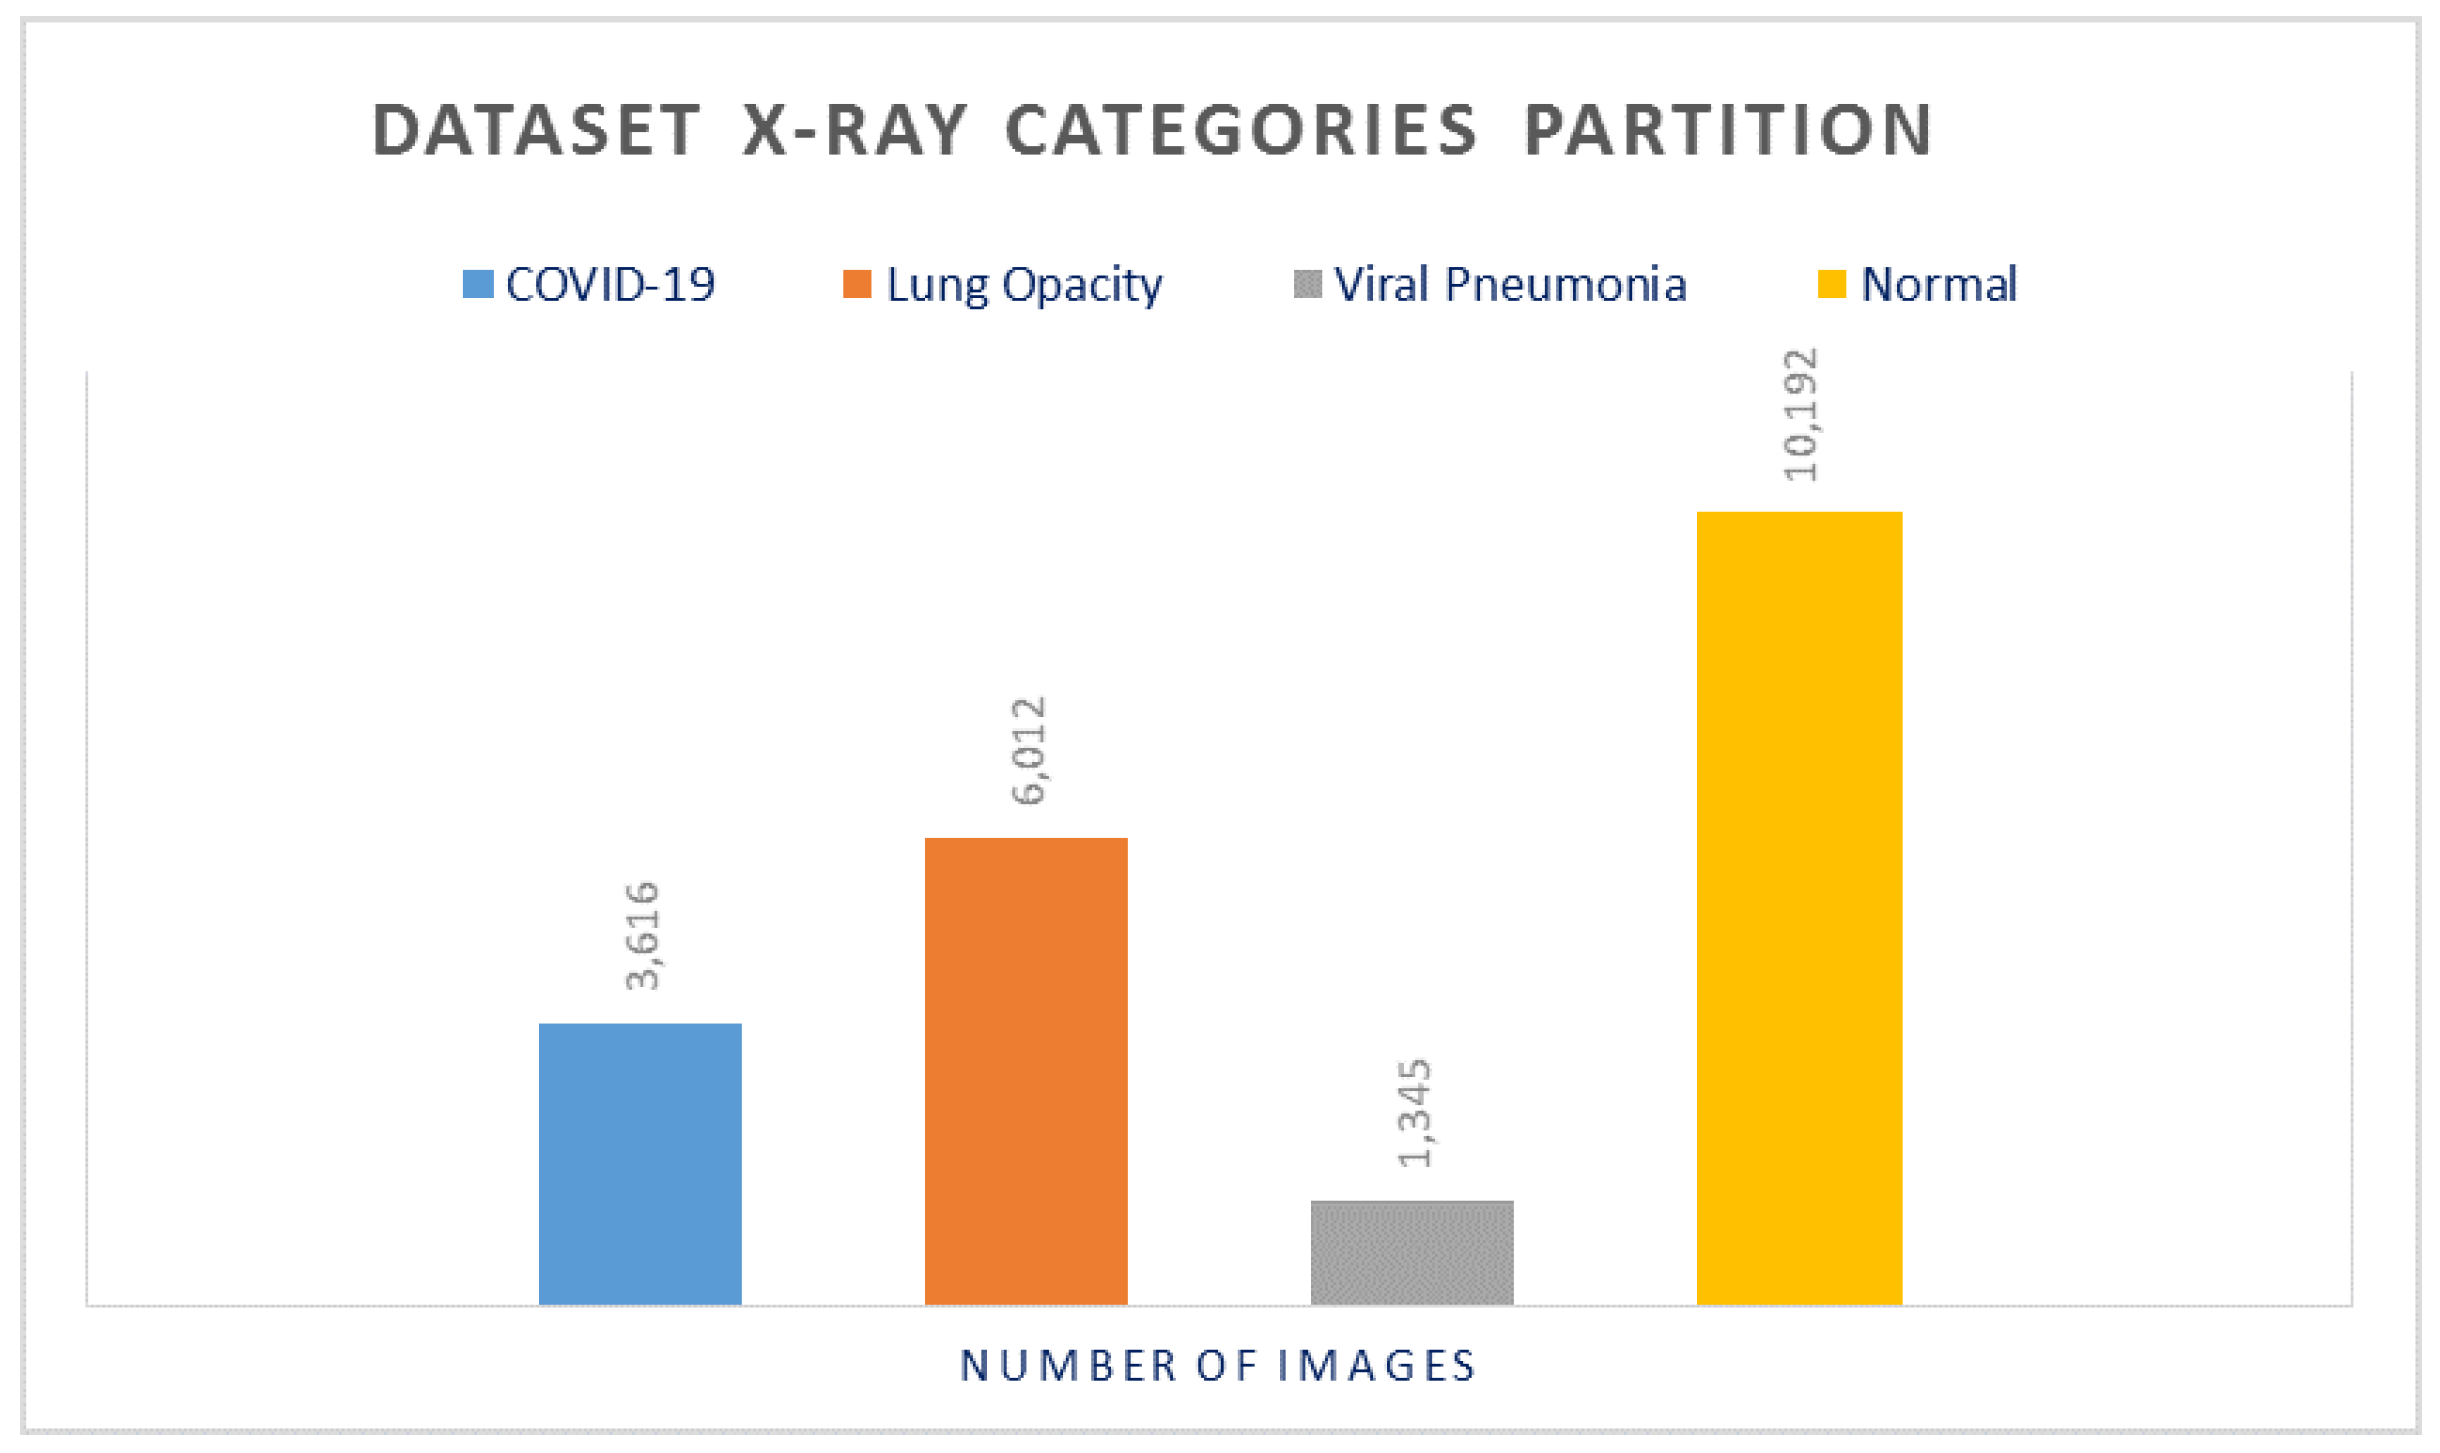

Figure 2 shows sample images from the studied dataset for each of these 4 categories. The COVID-19 images were collected from padchest dataset, Germany medical school, SIRM, GitHub, Kaggle, and Tweeter; the Normal images were collected from RSNA and Kaggle; Lung Opacity images were collected from the Radiological Society of North America (RSNA) CXR dataset; and the Viral Pneumonia images were collected from the Chest X-ray Images (pneumonia) dataset. The resolution of the various dataset varies in the range of 1112 × 624 to 2170 × 1953 pixels. However, these were preprocessed and scaled down to lower resolution of 299 × 299 pixels in the aggregated released dataset. All images are in the Portable Network Graphics (PNG) format. The frequency of the appearance in terms of number of images of each of the aforementioned categories varies for each of the 4 categories. The Normal category was most represented in the dataset with a count of 10,192 images, which represents ∼48% of the dataset. On the other hand, the count of the COVID-19 images is 3616, which represents ∼17% of the entire dataset. The Lung Opacity image count is 6012 which is equivalent to ∼28% of the entire dataset. The final category (Viral Pneumonia) is the least represented in the dataset, with a total of 1345 images representing ∼6% of the dataset. This category partitioning is depicted in

Figure 3. Although the dataset is balanced in terms of normal and abnormal images, it is imbalanced with respect to individual categories. To avoid any misinterpretation of results that may arise from the imbalanced data, we used multiple metrics (e.g., Accuracy, Precision, Recall, and F1-measure) for analyzing the performance of the classifiers.